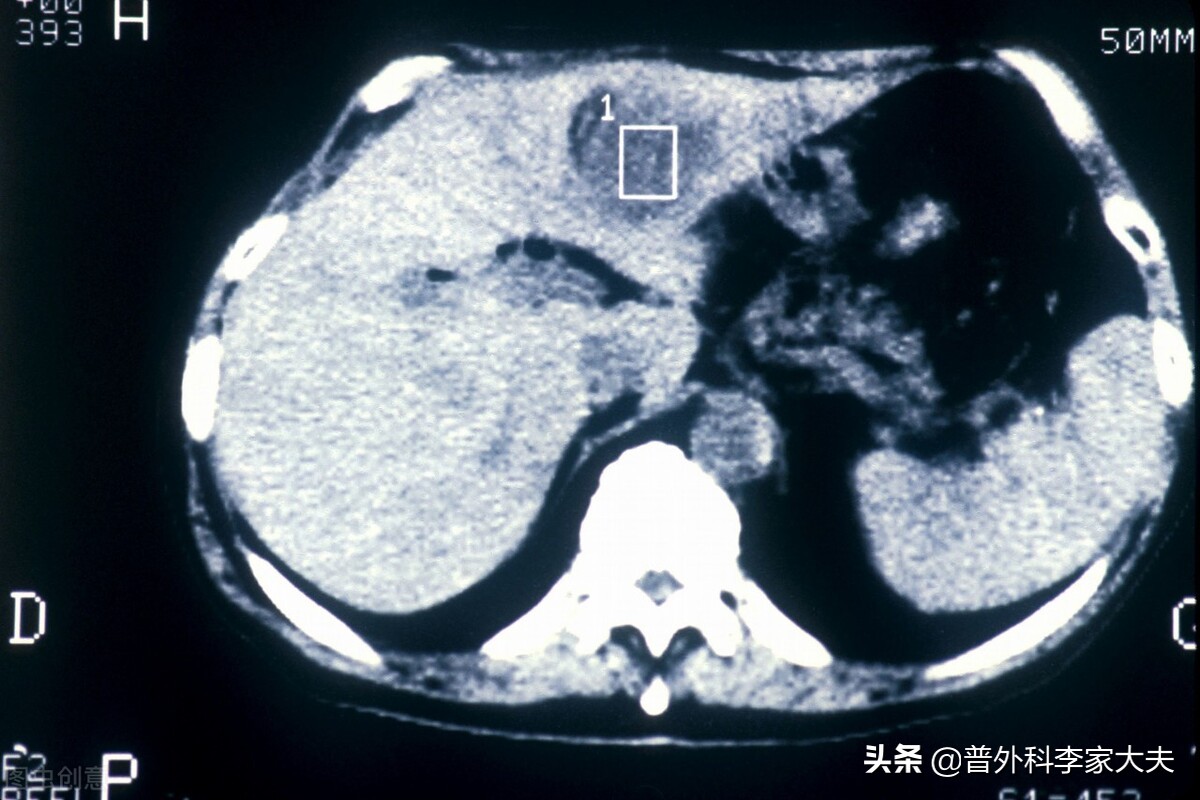

肝癌